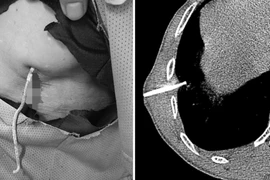

Viêm phổi mắc phải cộng đồng là bệnh lý nhiễm trùng phổi do sự tấn công của các tác nhân gây bệnh mắc phải trong cộng đồng. Bệnh không được điều trị tích cực rất dễ trở nặng và gây các biến chứng tại chỗ hoặc toàn thân.